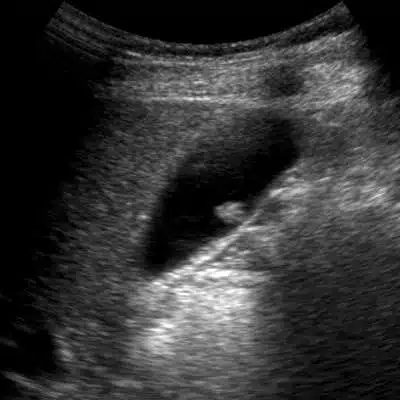

Πολύ συχνό φαινόμενο πλέον, λόγω της ολοένα αυξανόμενης υπερηχογραφικής μελέτης του ήπατος σαν προληπτικό έλεγχο, είναι η “τυχαία” ανεύρεση πολύποδα στην χολή! Ειναι πολύ εύλογη η ερώτηση πλέον του Έχω πολύποδα στη χολή – Τι να κάνω

- Πολύποδας στην χοληδόχο κύστη με μέγεθος πάνω από 6 χιλιοστά θα πρέπει να θεωρείται υποψήφιος για χειρουργική επέμβαση.

- Πολύποδας στην χοληδόχο κύστη που μεταβάλλει το μέγεθος σύντομα σε διαδοχικές μετρήσεις θεωρείται ύποπτος και πρεπει να χειρουργείται.

- Πολύποδας που αναπτύσσεται στον αυχένα της κύστεως και γειτνιάζει με τον κυστικό πόρο, θα πρεπει να χειρουργηθεί λόγω αποφράξεως της χοληδόχου κύστεως.

Η χειρουργική αντιμετώπιση είναι η λαπαροσκοπική χολοκυστεκτομή.